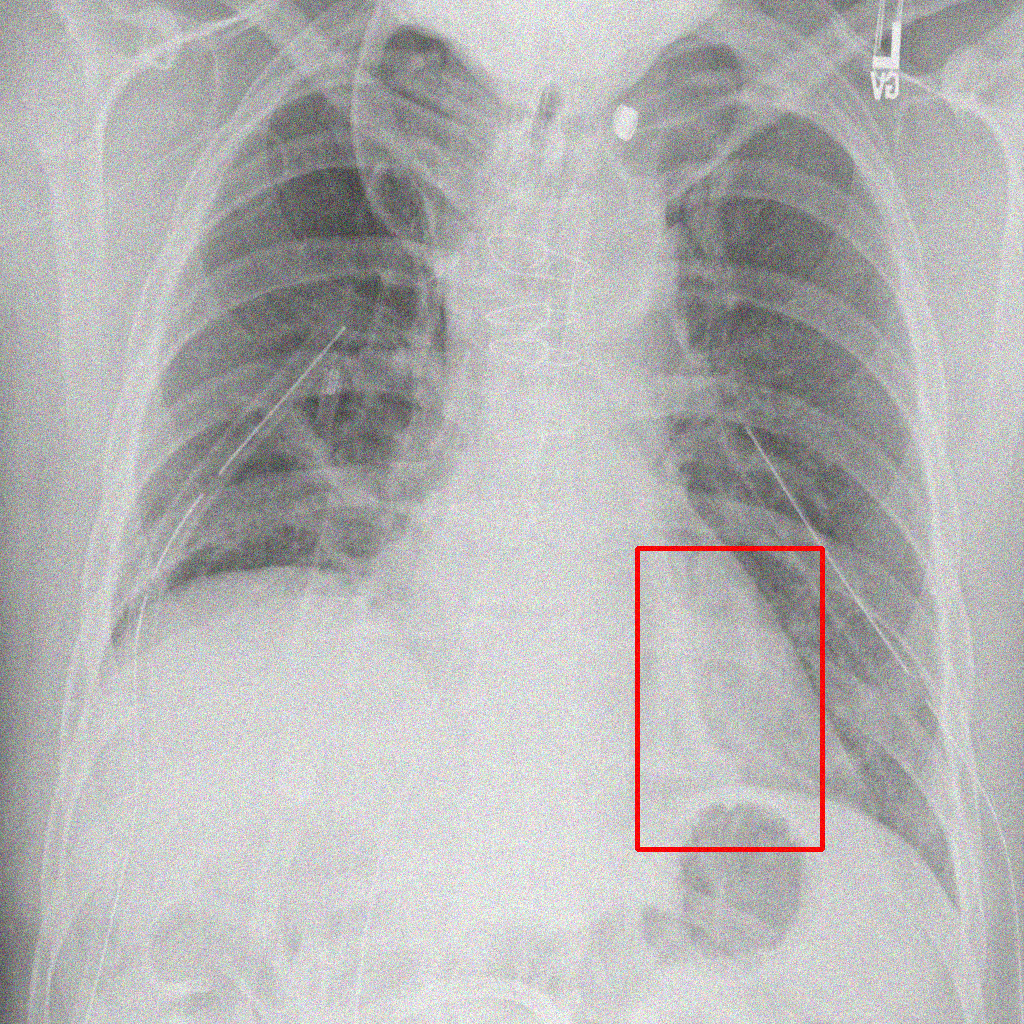

Object Rotation

X-ray GMAIMMbench Disease Diagnosis

Object Rotation - L0 (Original)

L0 (Original)

Question

Given the boxed region in the X-ray image, which abnormality is the image most indicative of?

A pneumothorax B pulmonary fibrosis C bone fracture D pleural effusion

Ground Truth: A. pneumothorax